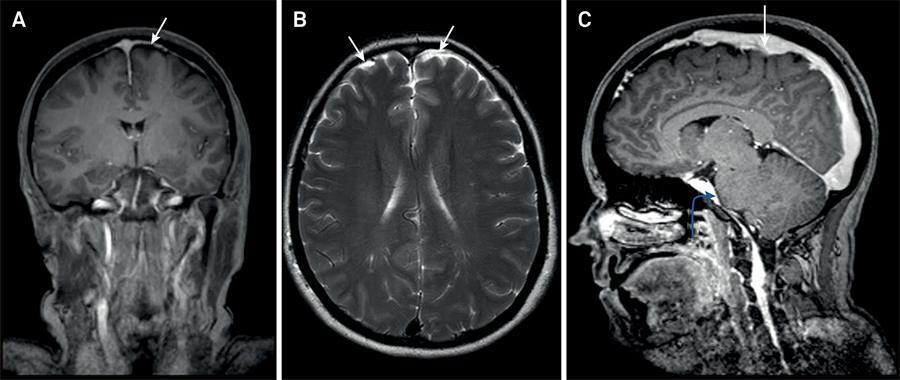

Qual o diagnóstico e por quê?

Hipotensão liquorica - hiperemia de pituitária - achatamento da ponte - realce paquimeningeo difuso

204

Qual o diagnóstico e por que?

Hipotensão liquorica à esquerda - redução do angulo mesencefalo-ponte - estreitamento do angulo entre veia de galeno e seio reto - achatamento da ponte - fossa posterior ''cheia''